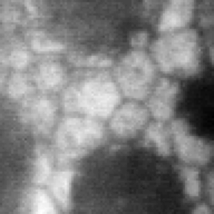

Specular microscopy assessment of the human corneal endothelium (CE) in Fuchs' dystrophy is challenging due to the presence of dark image regions called guttae. This paper proposes a UNet-based segmentation approach that requires minimal post-processing and achieves reliable CE morphometric assessment and guttae identification across all degrees of Fuchs' dystrophy. We cast the segmentation problem as a regression task of the cell and gutta signed distance maps instead of a pixel-level classification task as typically done with UNets. Compared to the conventional UNet classification approach, the distance-map regression approach converges faster in clinically relevant parameters. It also produces morphometric parameters that agree with the manually-segmented ground-truth data, namely the average cell density difference of -41.9 cells/mm2 (95% confidence interval (CI) [-306.2, 222.5]) and the average difference of mean cell area of 14.8 um2 (95% CI [-41.9, 71.5]). These results suggest a promising alternative for CE assessment.